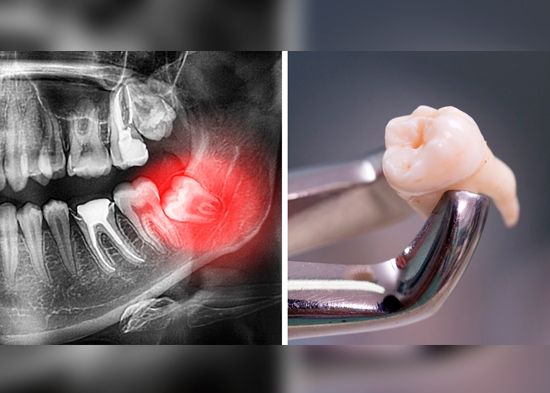

La retención puede ser parcial si se ve parte de la corona, pero no sale por completo y total cuando no atraviesa la encía, pero crece en ángulo contra la muela más próxima o crece en ángulo recto como si estuviera recostada.

Aunque es imposible saber si tus muelas del juicio están retraídas a menos que te realices una radiografía panorámica, sí puedes acudir con tu dentista para realizarte una limpieza dental por lo menos cada seis meses o una vez al año para evitar complicaciones a tiempo, por ejemplo, que enchuequen tus dientes.